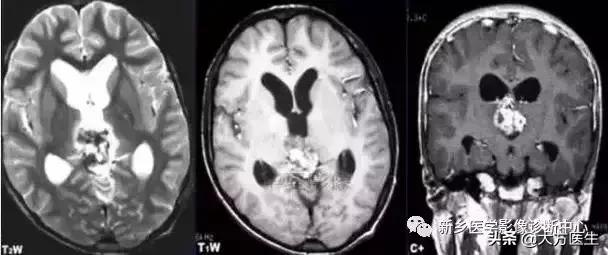

7、颅内结核(结核瘤)

多见于儿童和青年,多为继发。

CT:为等、高密度或混杂密度结节,可见钙化,轻度水肿,有占位效应。MR:T1WI包膜为等信号,瘤内凝固坏死为低信号。T2WI包膜可高可低,内部信号不均。